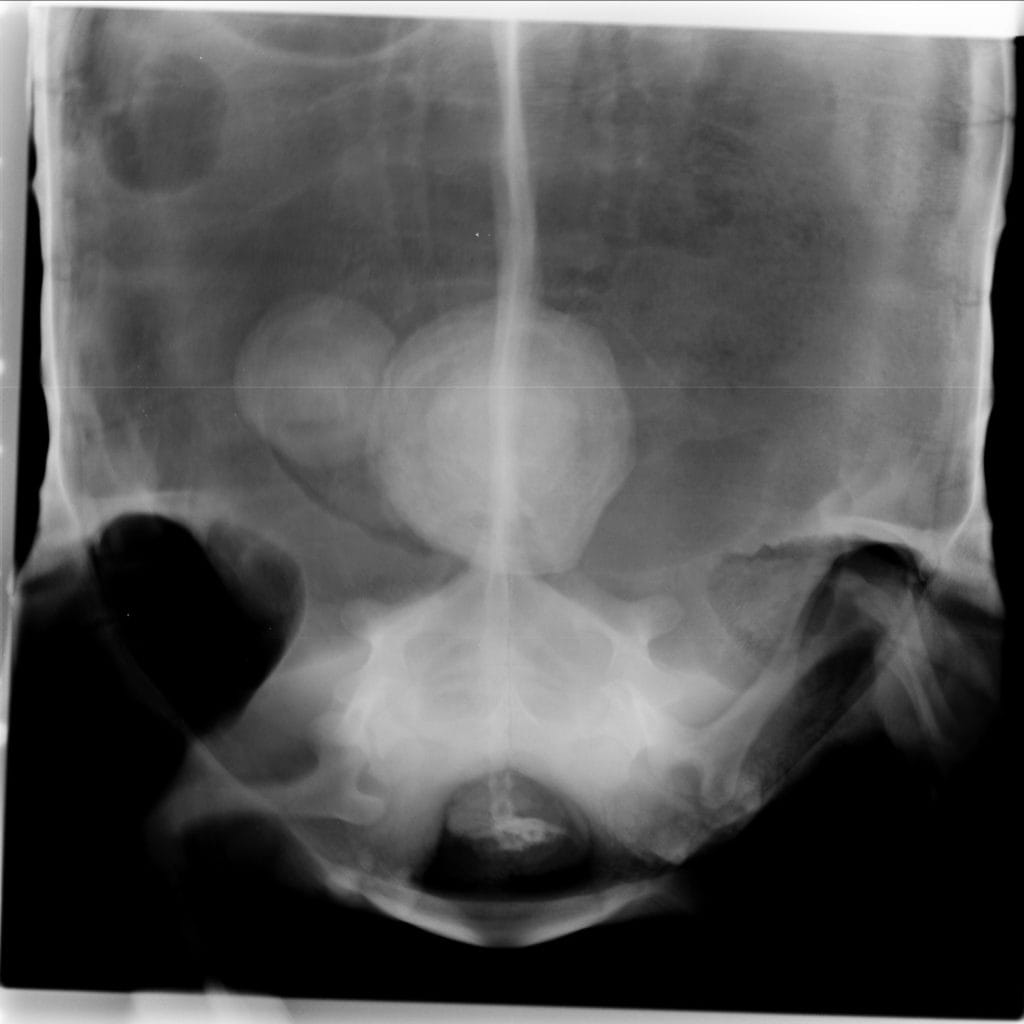

レントゲン検査では、膀胱に大きな結石が2つありました。

そのため、摘出することにしました。

今回は甲羅をあけて結石をとる方法を選択しました。それ以外にも足の付け根から手術を行う方法もあります。

結石はこのようにかなり大きいです。この子は手術後すぐにご飯を食べ始め、元気になって帰っていきました。